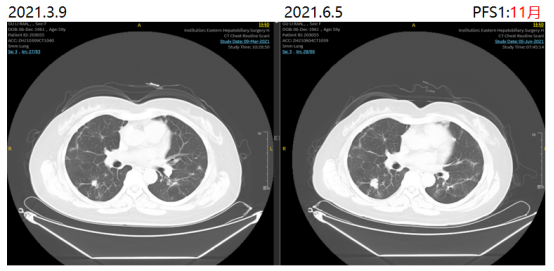

更换治疗方案为贝伐珠单抗+SIRI治疗。2021-06-05、2021-06-27、2021-07-20、2021-08-11分别予贝伐珠单抗500mg+伊立替康260mg 静滴+替吉奥60mg 2/日 q3w

治疗。

图2影像学复查结果